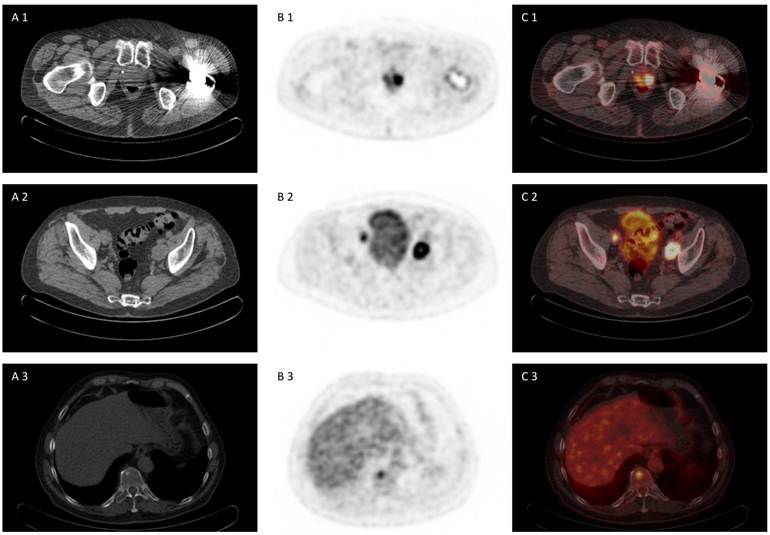

Fig 3

75 year old patient under of primary prostate cancer and increasing PSA> 40 ng/ml, referred for [18F]choline PET/CT for primary staging due to multiple negative biopies. [18F]choline PET/CT revealed advanced disease with multilocular prostate cancer, lymph node metastasis and bone metastasis (A 1-3) CT scan, (B 1-3) PET scan, (C 1-3) PET/CT fused images.